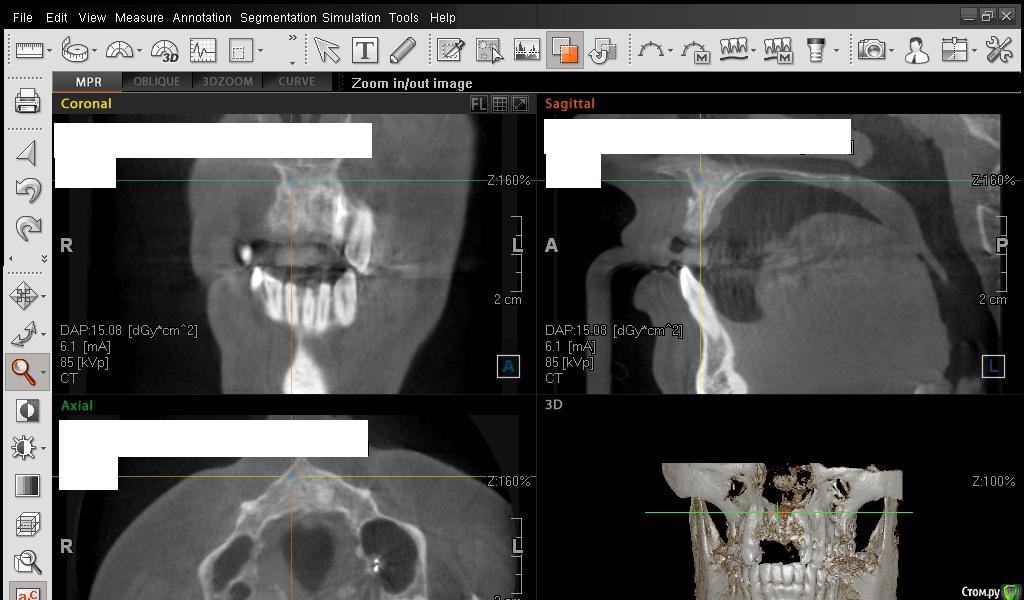

Сестричка Опубликовано 2 марта, 2015 Автор Поделиться Опубликовано 2 марта, 2015 Кажется поняла, проекция креста неправильная была? навела на область десны Ссылка на комментарий

Сестричка Опубликовано 2 марта, 2015 Автор Поделиться Опубликовано 2 марта, 2015 Еще пара срезов Ссылка на комментарий

АнтонТЛТ Опубликовано 2 марта, 2015 Поделиться Опубликовано 2 марта, 2015 Сам крест еще нужно повернуть, чтобы было одна полоса креста была параллельна краю челюсти Ссылка на комментарий